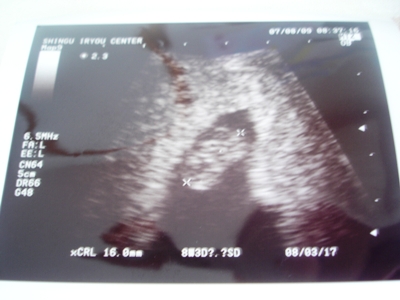

お腹のお豆の赤ちゃん、16㎜に成長してました

心拍も確認でき、元気に心臓も動いてたよ。

ちょうど、お豆ちゃんが動いてる所を見れて、感動です

ななの時は、お豆ちゃんが小さめだったので、生理日数からの予定日より1週遅らされたんだけど、今回は生理日数予定日相当の大きさだそうで、予定日は来年の3/17です。